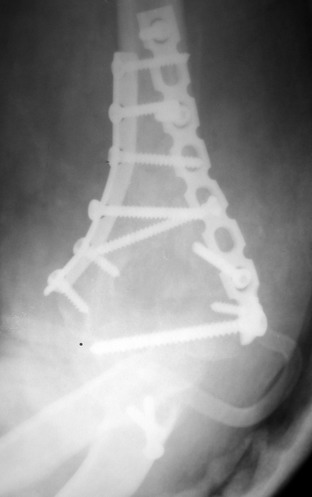

Примерный случай, только перелом был открытый, в задне-медиальной стороне рана около 2 см по характеру "изнутри кнаружи", неврологический статус со слабостью сгибания мизинца, также слабая абдукция и аддукция указательного пальца и сгибания в кисти.

Больному сделали обработку и наложили временный аппарат внешной фиксации плечо-предплечье.

На шестой день сделали открытую репозицию чрезлоктевым доступом двумя locking plate, локтевой нерв был ушибленным, после операции положительная динамика в Flexor Carpi Ulnaris. Фиксацию локтевого отростка произвели tension band technique с дополнительным шурупом.

Этапы операции на снимках....